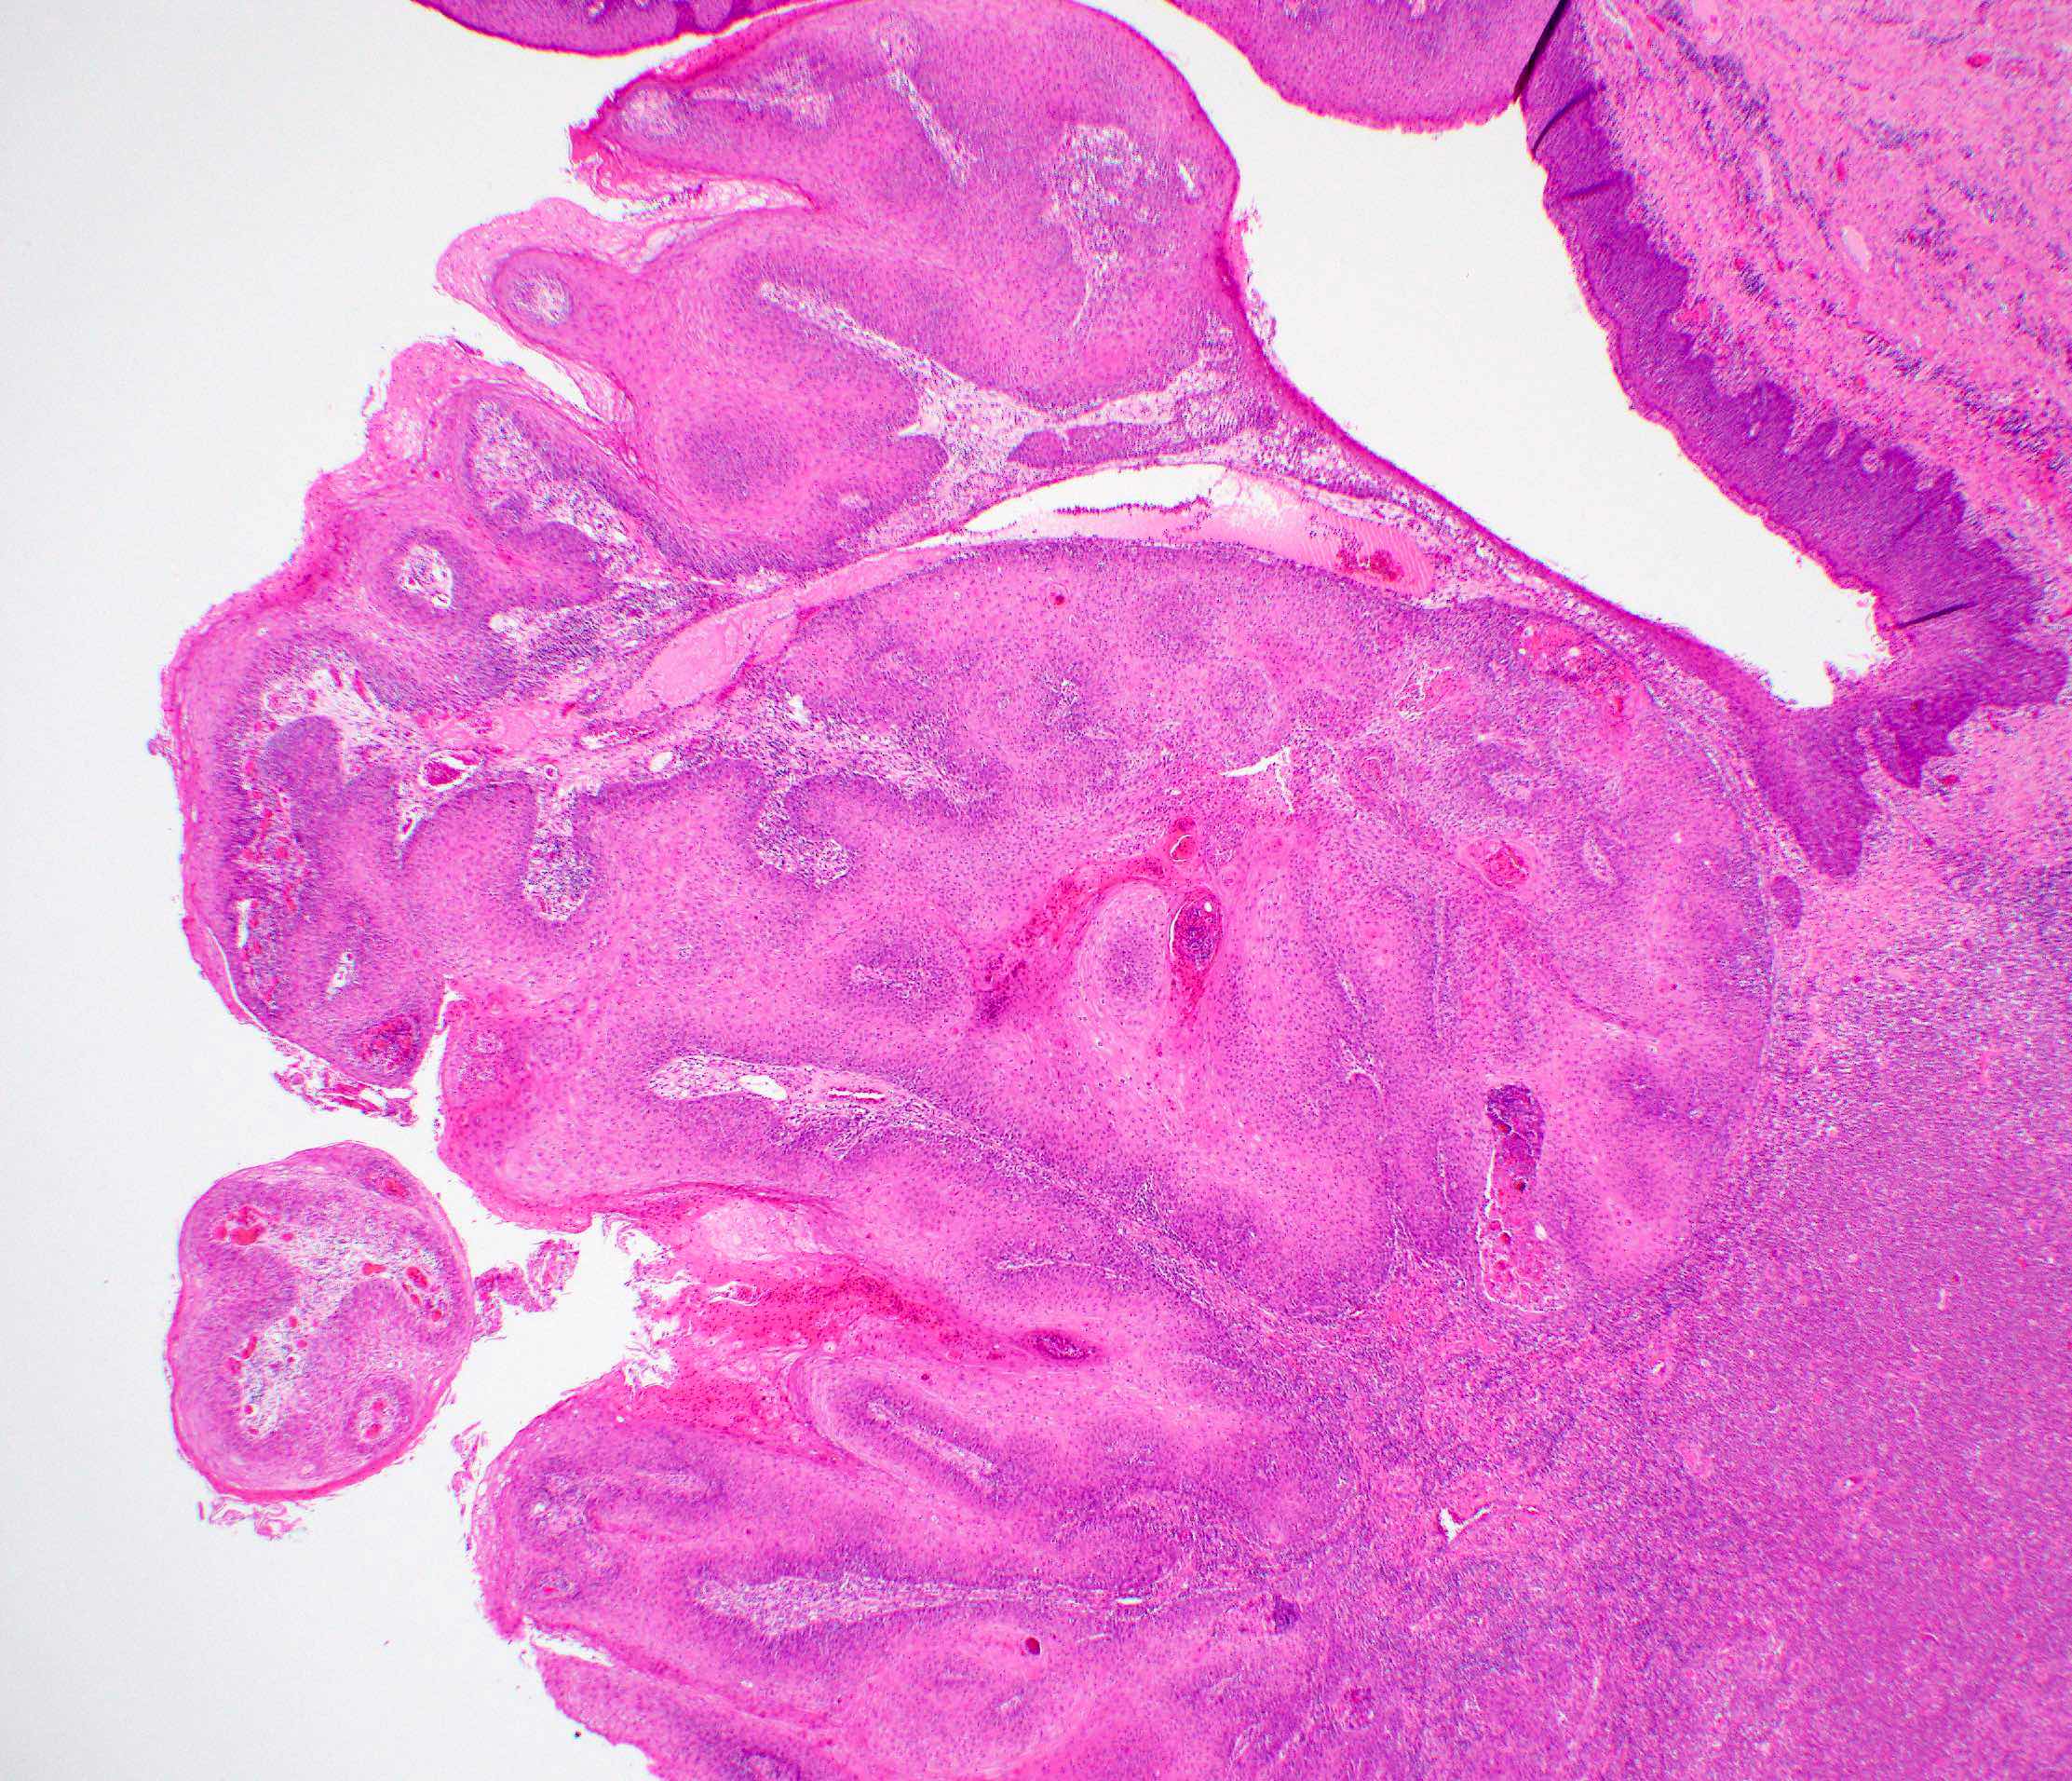

Gross description

- Macroscopic appearance varies with the morphologic type

- Common conventional squamous cell carcinoma shows an ulceroproliferative mucosal lesion with a firm gray-white infiltrative surface

- Verrucous and papillary squamous cell carcinomas demonstrate prominent exophytic, finger-like projections

- Spindle cell carcinoma generally presents as a mucosal polypoid lesion

Gross images

Microscopic (histologic) images

Contributed by Ruta Gupta, M.B.B.S., M.D.